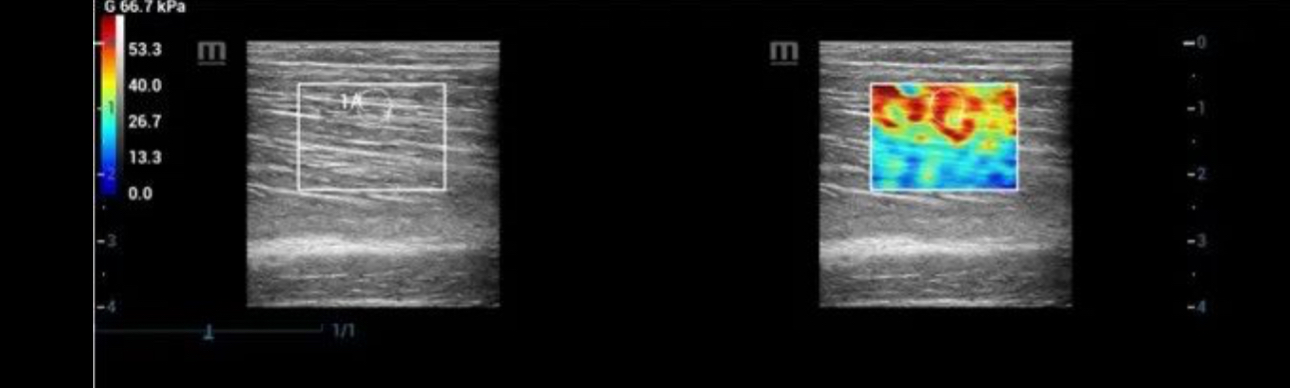

To provide doctors with more confidence, Mindray offers unique Shear Modulus “G” as elasticity metrics tool, besides the Young’s modulus “E” and Shear wave propagation velocity “Cs”. Direction ratio can also be measured with both longitudinal view and transverse view, which is designed especially for the evaluation of anisotropic tissues.

pc29-s4@web

Transverse View